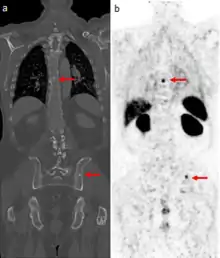

The main (67Ga) technique uses scintigraphy to produce two-dimensional images. After the tracer has been injected, images are typically taken by a gamma camera at 24, 48, and in some cases, 72, and 96 hours later.[23][24] Each set of images takes 30–60 minutes, depending on the size of the area being imaged. The resulting image will have bright areas that collected large amounts of tracer, because inflammation is present or rapid cell division is occurring. Single-photon emission computed tomography (SPECT) images may also be acquired. In some imaging centers, SPECT images may be combined with computed tomography (CT) scan using either fusion software or SPECT/CT hybrid cameras to superimpose both physiological image-information from the gallium scan, and anatomical information from the CT scan.

A common injection dose is around 150 megabecquerels.[25] Imaging should not usually be sooner than 24 hours as high background at this time produces false negatives. Forty-eight-hour whole body images are appropriate. Delayed imaging can be obtained even 1 week or longer after injection if bowel is confounding. SPECT can be performed as needed. Oral laxatives or enemas can be given before imaging to reduce bowel activity and reduce dose to large bowel; however, the usefulness of bowel preparation is controversial.[24]

In a normal scan, uptake of gallium is seen in wide range of locations which do not indicate a positive finding. These typically include soft tissues, liver, and bone. Other sites of localisation can be nasopharyngeal and lacrimal glands, breasts (particularly in lactation or pregnancy), normally healing wounds, kidneys, bladder and colon.[26]